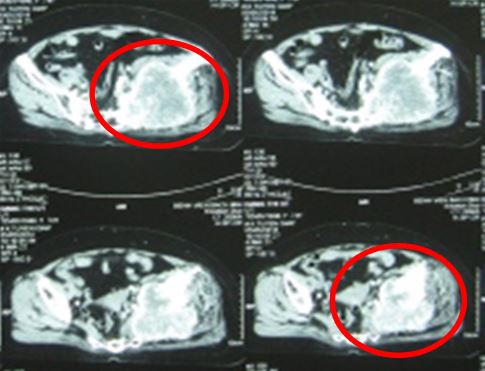

Hình 3. Hình ảnh chụp cắt lớp vi tính khung chậu sau xạ trị 1 tháng: kích thước tổn thương không tăng so với trước (9x10 cm), còn ngấm thuốc sau tiêm, có hoại tử trung tâm khối (vòng tròn vàng).

+ Kích thước khối tổn thương vùng xương cánh chậu và phần mềm bên trái giảm hơn trước (5x6 cm), mật độ chắc cứng, không gây đau.

Hình 9. Hình ảnh chụp cắt lớp vi tính vùng khung chậu: khối tổn thương tiêu xương cánh chậu

trái xâm lấn phần mềm kích thước 10,1 x 9,4cm.